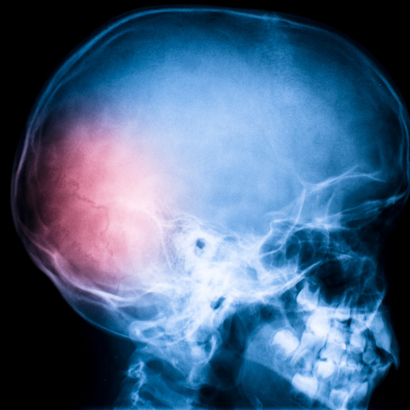

Published the results of the first study demonstrating the benefits of Omega 3 on the brain during recovery following traumatic brain injury. Omega-3s could be useful in reducing the long-term negative effects on the brain of traumatic brain injury. In particular, experts say the greatest effects could be achieved by giving the patient these fatty acids as early as the emergency room. Suggesting this are Michael Lewis, Parviz Ghassemi and Joseph Hibbeln, authors of a study published in the American Journal of Emergency Medicine1 in which, for the first time, the effects of Omega-3 administration during recovery after head injury were tested.

Interest in the potential benefits exerted by these nutrients following traumatic brain injury, a leading cause of traumatic death and disability, has also increased in recent years. The mortality associated with this type of trauma has been greatly reduced thanks to advances in surgical and intensive care methods, but there are still no specific therapies for dealing with the recovery phase. In fact, recovery goes through a period when the brain has to deal with problems such asinflammation and the presence of free radicals. In 2010, the U.S. Institute of Medicine (IOM) singled out Omega-3s as among the molecules whose benefits should be tested in this phase of convalescence, and the study by Lewis and colleagues is the first to try to shed light on this potential. The researchers administered high doses of these fatty acids to an adolescent recovering from a serious motorcycle accident. Specifically, 10 days after the head injury, the boy received 9.756 grams of EPA (eicosapentaenoic acid) and 6.756 grams of DHA (docosahexaenoic acid), the major food-derived Omega-3s. The therapy, the authors explained, allowed gradual improvements both cognitively and physically, so much so that 3 months after the accident the boy graduated from high school and 4 months after the injury was able to return home, where he continued the therapy throughout the following year.

The results obtained seem to indicate that Omega-3s provide the nutritional basis for the brain to heal. Since this is, however, the first case in which these fatty acids have been used during recovery after head injury, only after further research will it be possible to confirm the benefits of Omega-3s in recovering brain function.